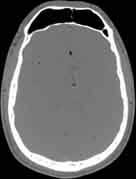

Visible Human male: Sectio transversalis 1078

NMR

Pd T1 T2